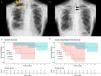

(a) Chest radiograph of a patient with PPFE at discharge, showing residual air space around the lung apex (arrows). (b) Chest radiograph of the same patient taken 1 month after surgical lung biopsy, showing a mediastinal shift toward the operative side (arrows). (c) Kaplan–Meier survival curves for the overall survival of patients grouped by diagnosis. P=0.03 by the log-rank test. (d) Kaplan–Meier survival curves for the acute exacerbation-free survival of patients grouped by diagnosis. P<0.01 by the log-rank test. Overall survival was defined as the number of days from surgical lung biopsy to death due to any cause or the last follow-up. Acute exacerbation-free survival was defined as the number of days from surgical lung biopsy to the diagnosis of acute exacerbation, death due to any cause, or last follow-up. The final follow-up was conducted in March 2024 to evaluate acute exacerbation, pneumothorax, and survival outcomes.

The modified Medical Research Council dyspnea scale was assessed following the established guidelines.8 The resected lung volume was calculated. If multiple lung sections were resected, their sum was considered as the volume of the resected lung. The diagnosis of acute exacerbation (AE) was made based on established criteria.9 Postoperative residual air space was identified on chest radiograph as in routine practice, after confirming the absence of air leaks and removal of the chest tube (Fig. 1a). All statistical analyses were performed using R version 4.1.3 (R Foundation for Statistical Computing, Vienna, Austria). All analyses were two-tailed, and statistical significance was set at P<0.05.

Kaplan–Meier curves showed that overall survival (OS) and AE-free survival post-SLB were significantly worse in the PPFE group than in the non-PPFE group (P=0.03; Fig. 1c and P<0.01; Fig. 1d, respectively). The median follow-up period was 791 and 2058 days for the PPFE and non-PPFE groups, respectively. The incidence rate of AE was higher in the PPFE group than in the non-PPFE group (20% vs. 6.9%, P=0.27). However, the association between SLB and AE was unclear because the two patients with PPFE developed AE more than 1-year post-SLB (1 and 3.7 years, respectively). Notably, both patients had lower lobe involvement, as observed on CT, which is reported to be associated with poorer survival outcomes.4 Comparison between patients with PPFE and those with IPF and NSIP, which were consistent with the overall results, are shown in the Additional Supplemental Files.

Patients with PPFE frequently develop pneumothorax, with a reported incidence rate of 25–89%,4,12–14 often accompanied by chronic residual air in the chest cavity.12 The high incidence of pneumothorax is believed to be associated with prominent negative intrathoracic pressure and high transpulmonary pressure due to stiff lungs.4 Therefore, SLB is hypothesized to exacerbate negative intrathoracic pressure and transpulmonary pressure in patients with PPFE by further reducing the volume of their stiff lungs. The current study supports this hypothesis, as the incidence rates of residual air space at discharge and ipsilateral pneumothorax during long-term follow-up were significantly higher in the PPFE group than in the non-PPFE group. Lung collapse during SLB and the volume loss in the stiff lung may require time to re-inflate, potentially leading to a residual air space. After healing of a relatively large air space, a mediastinal shift was observed (Fig. 1b), suggesting exacerbated negative intrathoracic pressure. Additionally, OS post-SLB was worse in the PPFE group than in the non-PPFE group, which included six patients with IPF. Exacerbated negative intrathoracic pressure may have been associated with poor outcomes. However, patients with progressive PPFE exhibit poor prognoses, regardless of SLB.13 Further investigation is needed to determine whether SLB contributes to the development of pneumothorax and worsens prognosis in patients with PPFE.